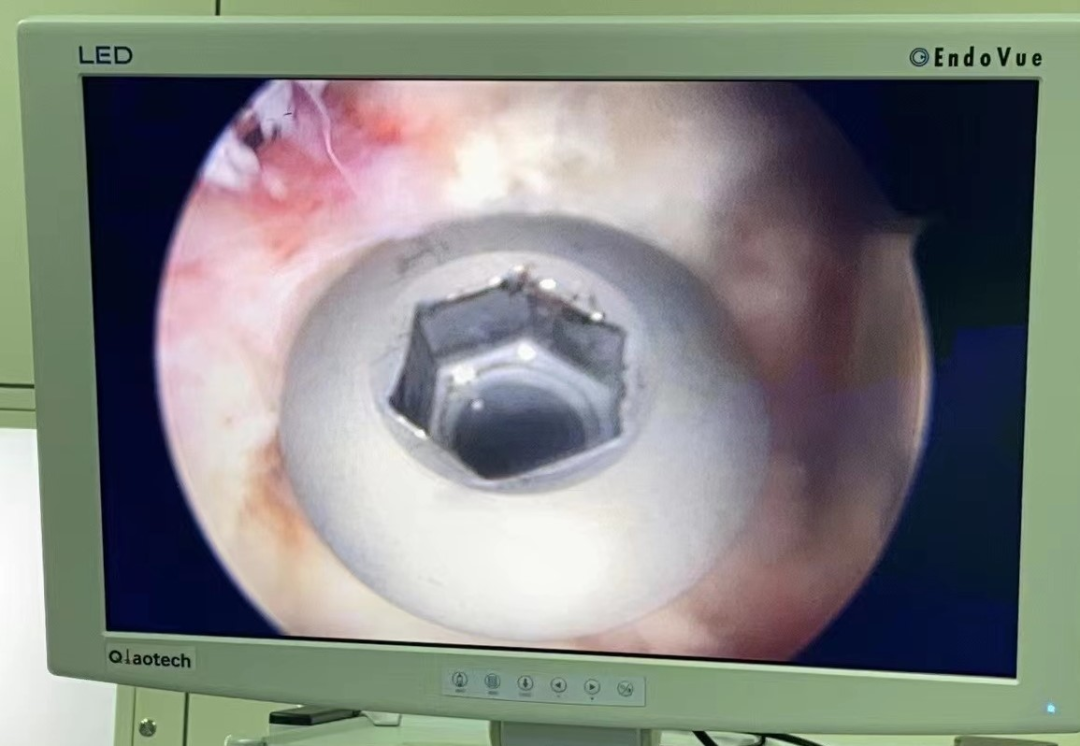

近日,我院骨科成功开展肩关节镜下大结节骨折内固定+肩袖修补术。患者,男,46岁,因右肩摔伤肿痛活动受限入院。CT示:右肱骨大结节骨折。MR检查提示:右冈上肌腱损伤。完善术前准备后,行“肩关节镜下右肱骨大结节骨折内固定术+肩袖修补术”,手术非常顺利,术后我院康复团队介入早期康复,加快了患肩功能锻炼的进程,患肩功能恢复良好。

肱骨大结节骨折是肱骨近端骨折中常见的骨折类型之一,肱骨大结节骨折后肩袖肌腱的力臂遭到破坏,特别是在肩关节外展时,严重影响了肩关节功能。移位的大结节减低了肩峰下间隙,导致肩关节在外展活动时出现撞击,使肩关节的功能和活动范围受到影响。因此,治疗移位明显的肱骨大结节骨折不但需要坚强固定,同时需要解剖复位。随着肩关节镜的发展,关节镜下治疗大结节骨折已被越来越广泛的应用。关节镜下可采用空心钉、克氏针、双排锚钉(双线桥)等方式进行固定,根据不同骨折类型可以多种术式相互结合使用。对肱骨大结节骨折块较小、粉碎严重的骨折难以达到解剖复位,坚强固定,术后容易出现内固定失效,因此对于肱骨大结节粉碎性骨折,建议采用双排锚钉缝线桥技术固定大结节骨折,内、外排带线锚钉的尾线交织成“网状”线桥,将粉碎的大结节骨折块完全覆盖在骨折的足印区,达到精确复位,坚强固定。缝线桥技术的适应证为单纯的肱骨大结节骨折,骨折粉碎性,骨折范围直径<3 cm。对于较大骨折块,可以选用带线锚钉缝线桥技术固定肱骨大结节骨折时,结合空心钉固定。肩关节镜下双排锚钉缝线桥技术治疗肱骨大结节撕脱骨折,对肩关节外科医生技术要求较高,具有一定学习曲线。肩关节镜下不仅能有效固定大结节骨折,还可修复合并损伤如Bankart损伤、肱二头肌长头肌腱损伤、SLAP损伤,效果令人满意,目前是一种有效的肱骨大结节撕脱骨折的微创治疗方案。

肩关节镜技术以其术口小、不损伤原有解剖结构、精准度高及术后康复快等优势,而被更多患者接受。但在临床诊疗中,需要对肱骨大结节解剖学特点、损伤机制及骨折分型等方面充分认识,选择合适手术适应证,熟练掌握肩关节镜肱骨大结节撕脱骨折固定技术要点,才能更好地应用肩关节镜技术治疗肱骨大结节骨折,从而减少手术损伤、加速患者术后康复、减少相应手术并发症。关节镜已逐渐成为肩关节疾病的重要的常规治疗手段。随着该技术的普及推广,越来越多的骨科医生掌握此项技术,从而使越来越多的患者从中受益。